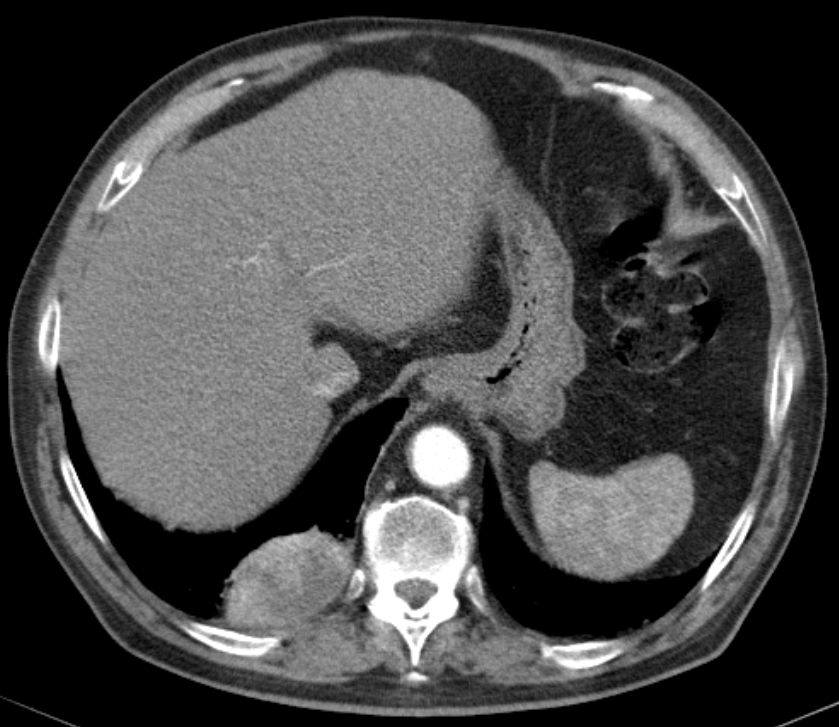

| Schwanom des Thorax | 79-jähriger Mann mit einer unklaren Raumforderung im rechten Unterlappen. Thorakoskopisch großer nekrotisch zerfallender Tumor. Pleurale Raumforderung i.S. einer Abklatschmetastase. Histologisch spindelzellige Proliferate, vergrößerte hyperchromatische atypisch geformte Zellkerne. Z.T. mehrkernige Riesenzellen. Im Zentrum ausgedehnter nekrotischer Zerfall. Histochemie: CD34, Panzytokeratin, EMA, Alfa-Aktin, Caldesmon, HMB45, Melan A und Zytokeratin A negativ. Vimentin überwiegend positiv | ||

Das CT mit Kontrastmittel zeigt im Randbereich eine unregelmäßige Anreicherung.![]() |

Im Lungenfenster keine deutliche Invasion aber breitflächiger Kontakt zur Pleura.![]() | ||

Das PET-CT zeigt massiven Stoffwechsel in der Randzone des Tumors.![]() |